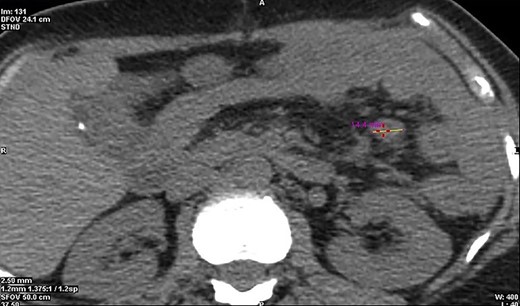

CT cross-section illustrating a diameter of 14.4 mm of the malignant neuroendocrine tumour.